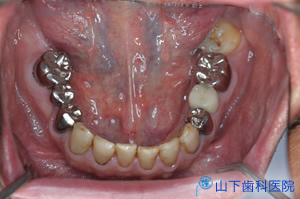

| 治療前 | 治療後 |

| 「入れ歯」では思うように噛めず、気持ち悪い。前歯で噛んでいるがぐらぐらしてきた。 残る歯もすっきりしない所が多々あり、今後に不安を抱えて来院されました。 |

| 上下の奥歯が咬み合うことで決まる咬合が不安定で、下の前歯が上の前歯を突き上げています。 予知性がない右下、左上の4番目を抜歯して落ち着いた状態です。 |